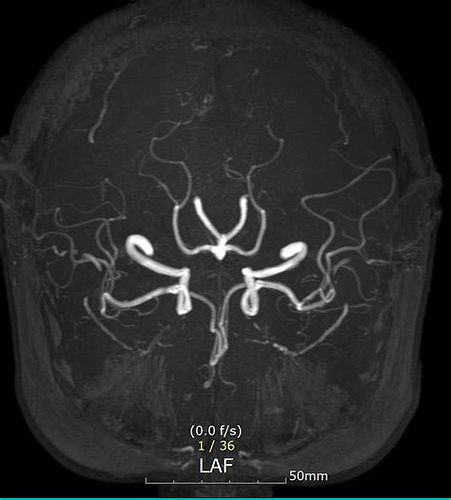

뇌 MRA (뇌혈관 자기공명영상) 검사

- 비급여 기준

- MRI와 유사하게 40만 원 선으로 안내하는 병원 사례 있음.

- 병원마다 차이가 있으니 사전 확인 필요.

MRA 검사 비용

- 비급여(보험 미적용) 기준

- 대학병원: 비조영 MRA 35~60만 원, 조영 MRA 50~80만 원.

- 종합병원: 30~50만 원(비조영), 45~70만 원(조영).

- 영상의학 전문병원: 25~40만 원(비조영), 40~65만 원(조영).

- 지역 의원: 20~35만 원(비조영), 35~55만 원(조영)

- 실제 예시: 포항시 에스포항병원 뇌 MRA 48만 원, 사랑의병원 58만~50만 원(검진시 할인가)

- 건강보험 적용 시

- 본인 부담금 약 20만~40만 원(조건 충족 시).

MRI + MRA 동시 검사

- 동시 촬영 시 60만~100만 원(비급여), 보험 적용 시 30만~50만 원 수준.